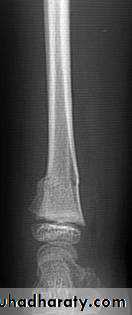

34Stress (fatigue) #

# that occurs in normal bone by repetitive stresses

> in athletes, ballet dancers & military recruits

Common sites: pars interarticularis of L5, FN, proximal tibial shaft, distal fibular shaft,calcaneum, MTBs

XR: early : -ve… few weeks : transverse defect ± periosteal new bone

Bone scanDDx: OM, OSa

Tx :immobilize & avoid painful activity